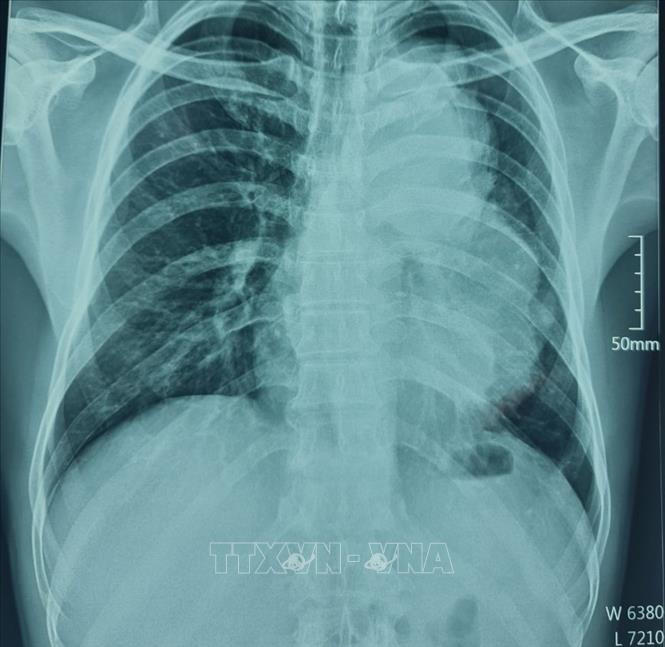

![]() |

| Hình ảnh cận lâm sàng bệnh nhân A. B (50 tuổi, trú xã Măng Bút, huyện Kon Plông, tỉnh Kon Tum) có u trong lồng ngực kích thước lớn. Ảnh: TTXVN phát |